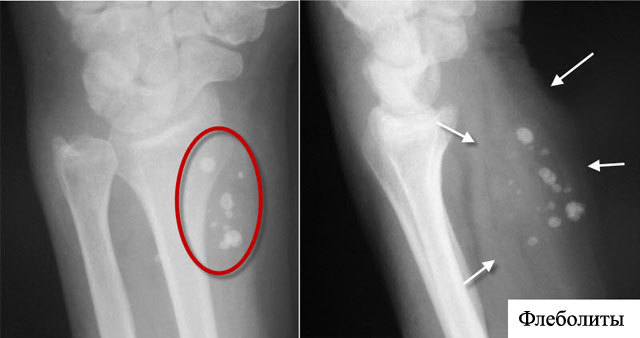

Флеболит это небольшие частички закальцинированных тромбов, которые образовываются в венах. На рентгеновских снимках проявляются в виде белых пятен.

- Рентген. Снимок позволяет определить точную локализацию камней. Они имеют овальную форму, характерную концентрацию.

Кальциевые камни органов или вен малого таза наиболее часто обнаруживаются случайно на рентген-снимках в виде мелких камнеобразных уплотнений. Для определения точной локализации, а также размера образований проводят магнитно-резонансную или компьютерную томографию, позволяющую оценить их особенности в различных проекциях.

Множественные флеболиты могут быть обнаружены в сосудистых опухолях (гемангиомах) при рентгенографии, в венах ног путем ультразвукового или рентгеновского исследования.

- Рентгенография определяет флеболиты в проекции малого таза в виде округлых теней с множеством слоев. Важным диагностическим признаком является наличие радиопрозрачного центра (симптом «хвоста кометы»).

- Рентгенография малого таза. На обзорных снимках рентгеноконтрастные флеболиты видны как овальные структуры с концентрическими кольцами («расслоениями»). Важными диагностическими признаками тазовых камней принято считать наличие радиопрозрачного центра, симптом «хвоста кометы».